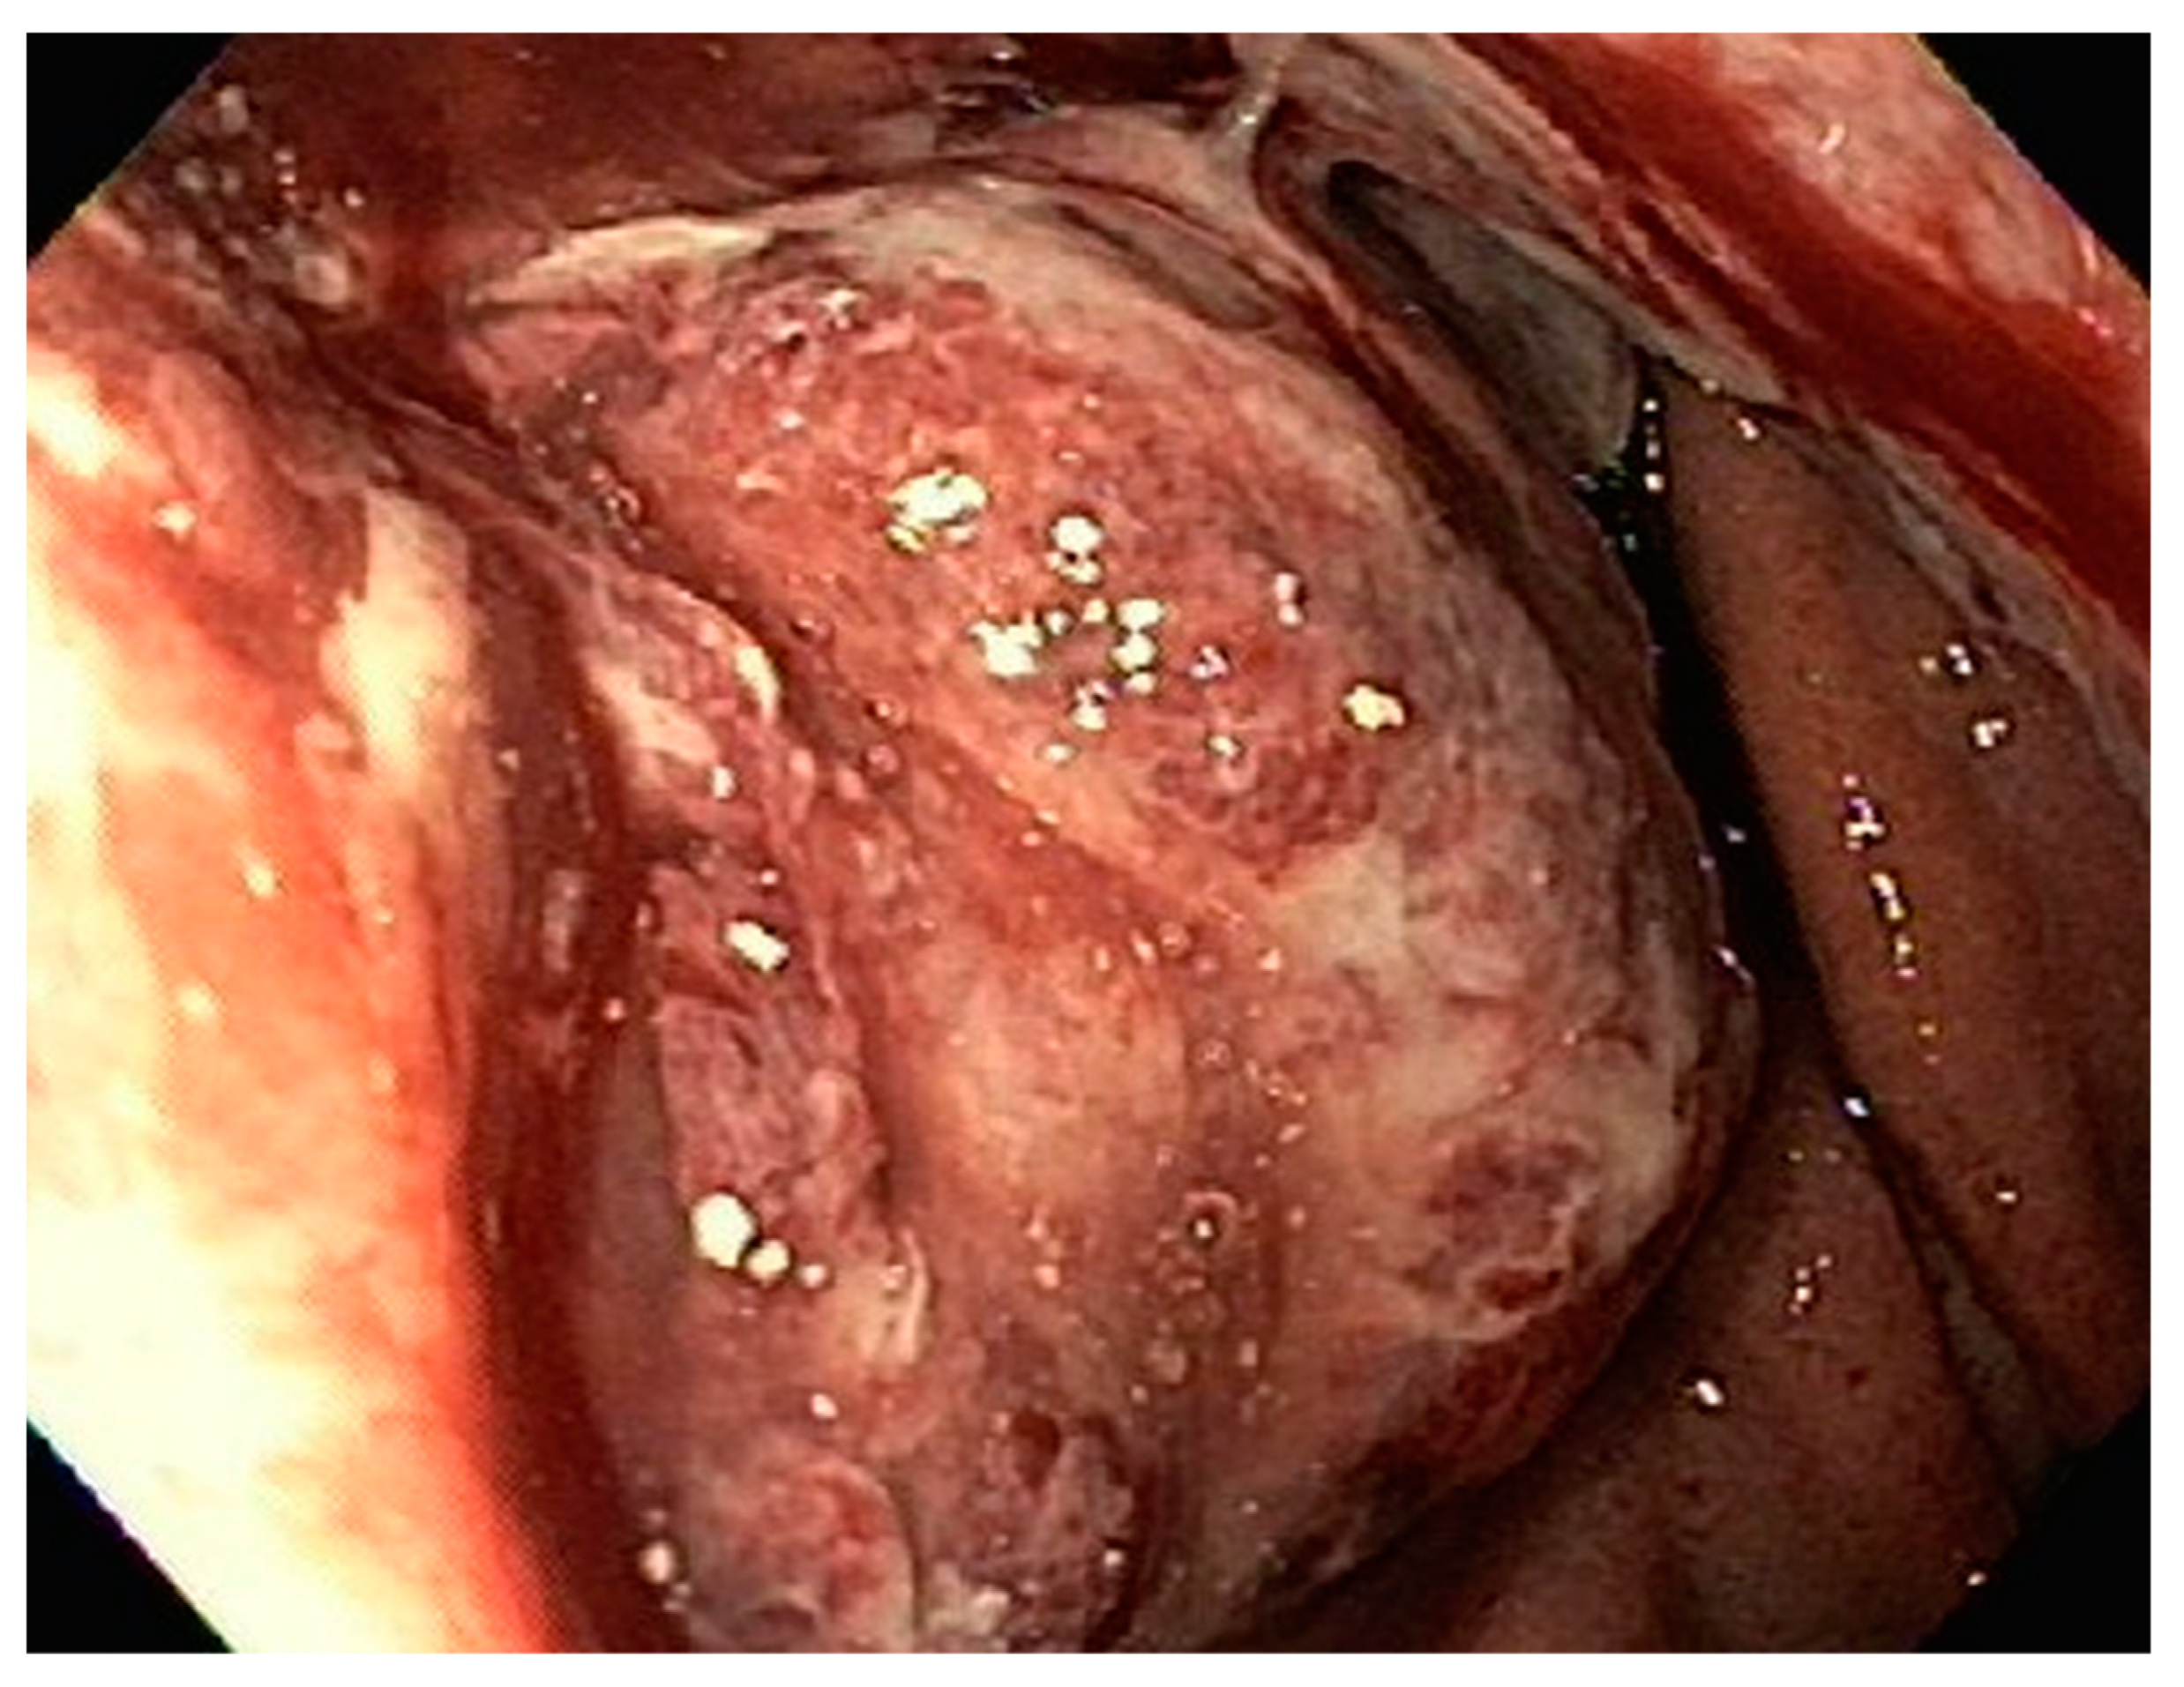

| 2 | M | 84 | Lymphoid | Fundus and cardia | Ulcerated and necrotic mass | Liver, urinary bladder | Diffuse large B-cell lymphoma | None | Death in 2 months after EGD diagnosis of metastasis |

| 4 | F | 73 | Kidney | Fundus and body | Multiple large friable masses | Liver and lungs | Clear cell renal carcinoma | Nephrectomy, chemotherapy, immunotherapy (Axitinib) | Death 10 days after EGD diagnosis of metastasis |